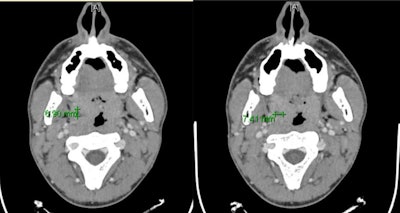

A computed tomography (CT) scan confirmed the abscess. The man was admitted to the hospital and given high-dose intravenous antibiotics and steroid therapy to manage the abscess and to limit healthcare workers' exposure to SARS-CoV-2, they wrote.

Two days after his discharge from the hospital -- 14 days from the start of his symptoms -- the patient tested negative for the novel coronavirus. The peritonsillar abscess had been treated successfully, his oral cavity was normal, and he could eat and drink without difficulty four days after his discharge. Four days later, a CT scan confirmed the complete resolution of the abscess and the antibiotics were stopped, according to the authors.